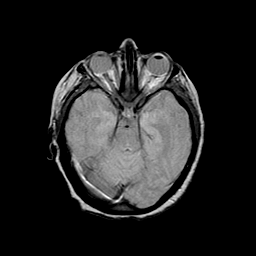

Basal Ganglia Calcification: proton density-weighted MR -- Slice #6

[Home][Help][Clinical] Slice 6